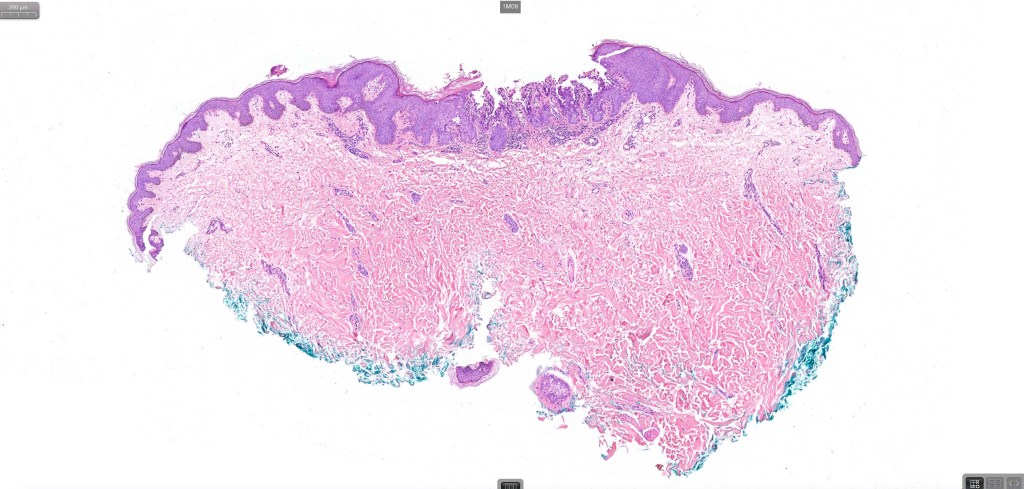

Focal acantholytic dyskeratosis

This term is used for localized acantholysis with dyskeratosis occuring as an incidental finding is a specimen excised for some other lesion. The image belw came from a adjacent univolved skin in an excision specimen